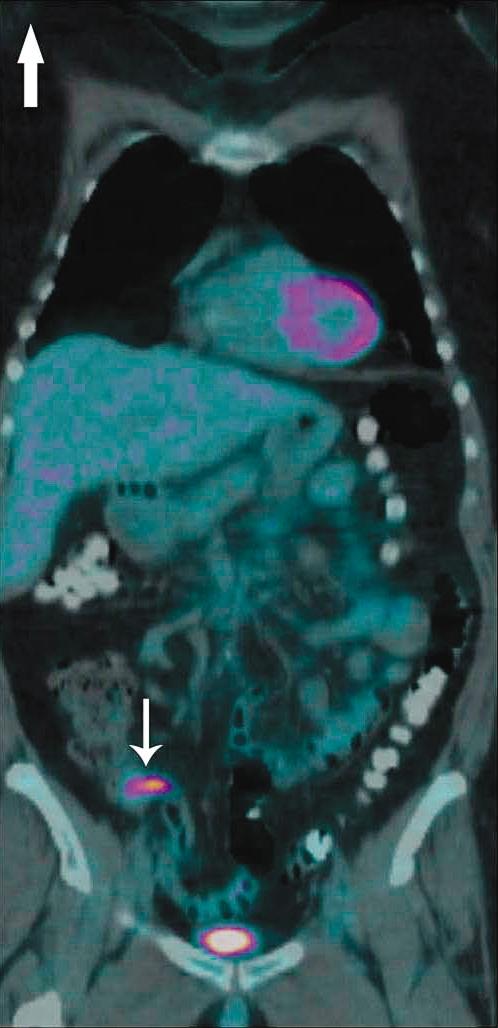

Acute appendicitis from metastatic small cell lung cancer.

https://cdn.ncbi.nlm.nih.gov/pmc/blobs/e8fe/3298197/c45ae31e7982/wjem-13-01-33w-f01.jpg